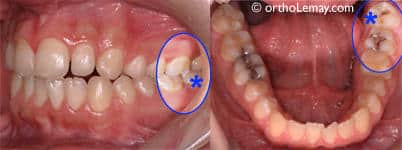

Alors pourquoi s’en prend t-on aux dents de sagesse ? Si elles existent c’est bien qu’elles doivent servir à quelque chose n’est-ce pas ? Effectivement mais bien des dentistes décident de les faire enlever à leurs patients pour anticiper un problème : infection lors de la pousse, déplacement des autres dents etc… Il arrive en effet que les dents de sagesse n’aient plus beaucoup de place pour pousser et qu’elles soient obligées de pousser les dents déjà en place. Ces troisièmes molaires sont donc enlevées de manière quasi systématique car ces opérations sont un business très lucratif !

En France, 1/3 des dents de sagesse sont retirées alors qu’elles auraient très bien pu rester dans votre bouche… de plus, les dents de sagesse ont une réelle utilité dans le sens où elles assurent le maintien de l’ensemble de la dentition. Il n’est pas rare que l’on voit suite à des extractions préventives arriver des problèmes de dents qui se déchaussent.